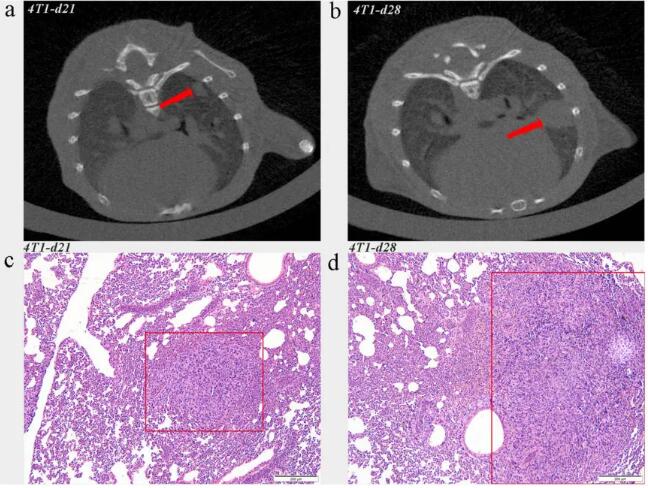

在本研究中,將 4T1 乳腺癌細胞接種到 Balb/c 小鼠耦合的腹部乳腺中,建立腫瘤模型。把小鼠分為對照組和 4T1 實驗組,然后就要用到 Micro-CT(Hiscan XM,Suzhou Hiscan Information Thechnology Co.,Ltd)對接種腫瘤細胞的小鼠重復(fù)檢查。下圖分別顯示了 21 天和 28 天后實驗組的肺轉(zhuǎn)移情況。

圖 1.2 肺轉(zhuǎn)移小鼠具有代表性的 Micro-CT 圖像和 H&E 染色。ac CT 圖像和 H&E 染色在部分 4T1 荷瘤小鼠第 21 天檢測到肺轉(zhuǎn)移。bd CT 圖像和 H&E 染色顯示腫瘤接種第 28 天肺轉(zhuǎn)移明顯。

實驗發(fā)現(xiàn),隨著原發(fā)腫瘤的生長,CT 圖像中有細微的、均勻的彌漫性混濁,而肺組織的 H&E 染色顯示炎性細胞浸潤增加。在第 21 天和第 28 天,CT 圖像和 H&E 染色顯示所有荷瘤小鼠都有明顯的炎癥細胞浸潤。結(jié)果表明,Micro-CT 可以用來觀察肺內(nèi)微環(huán)境的變化和轉(zhuǎn)移情況。此外,與僅提供轉(zhuǎn)移過程快照的組織病理學(xué)分析不同,Micro-CT 還可以捕捉到來自動物的縱向信息。